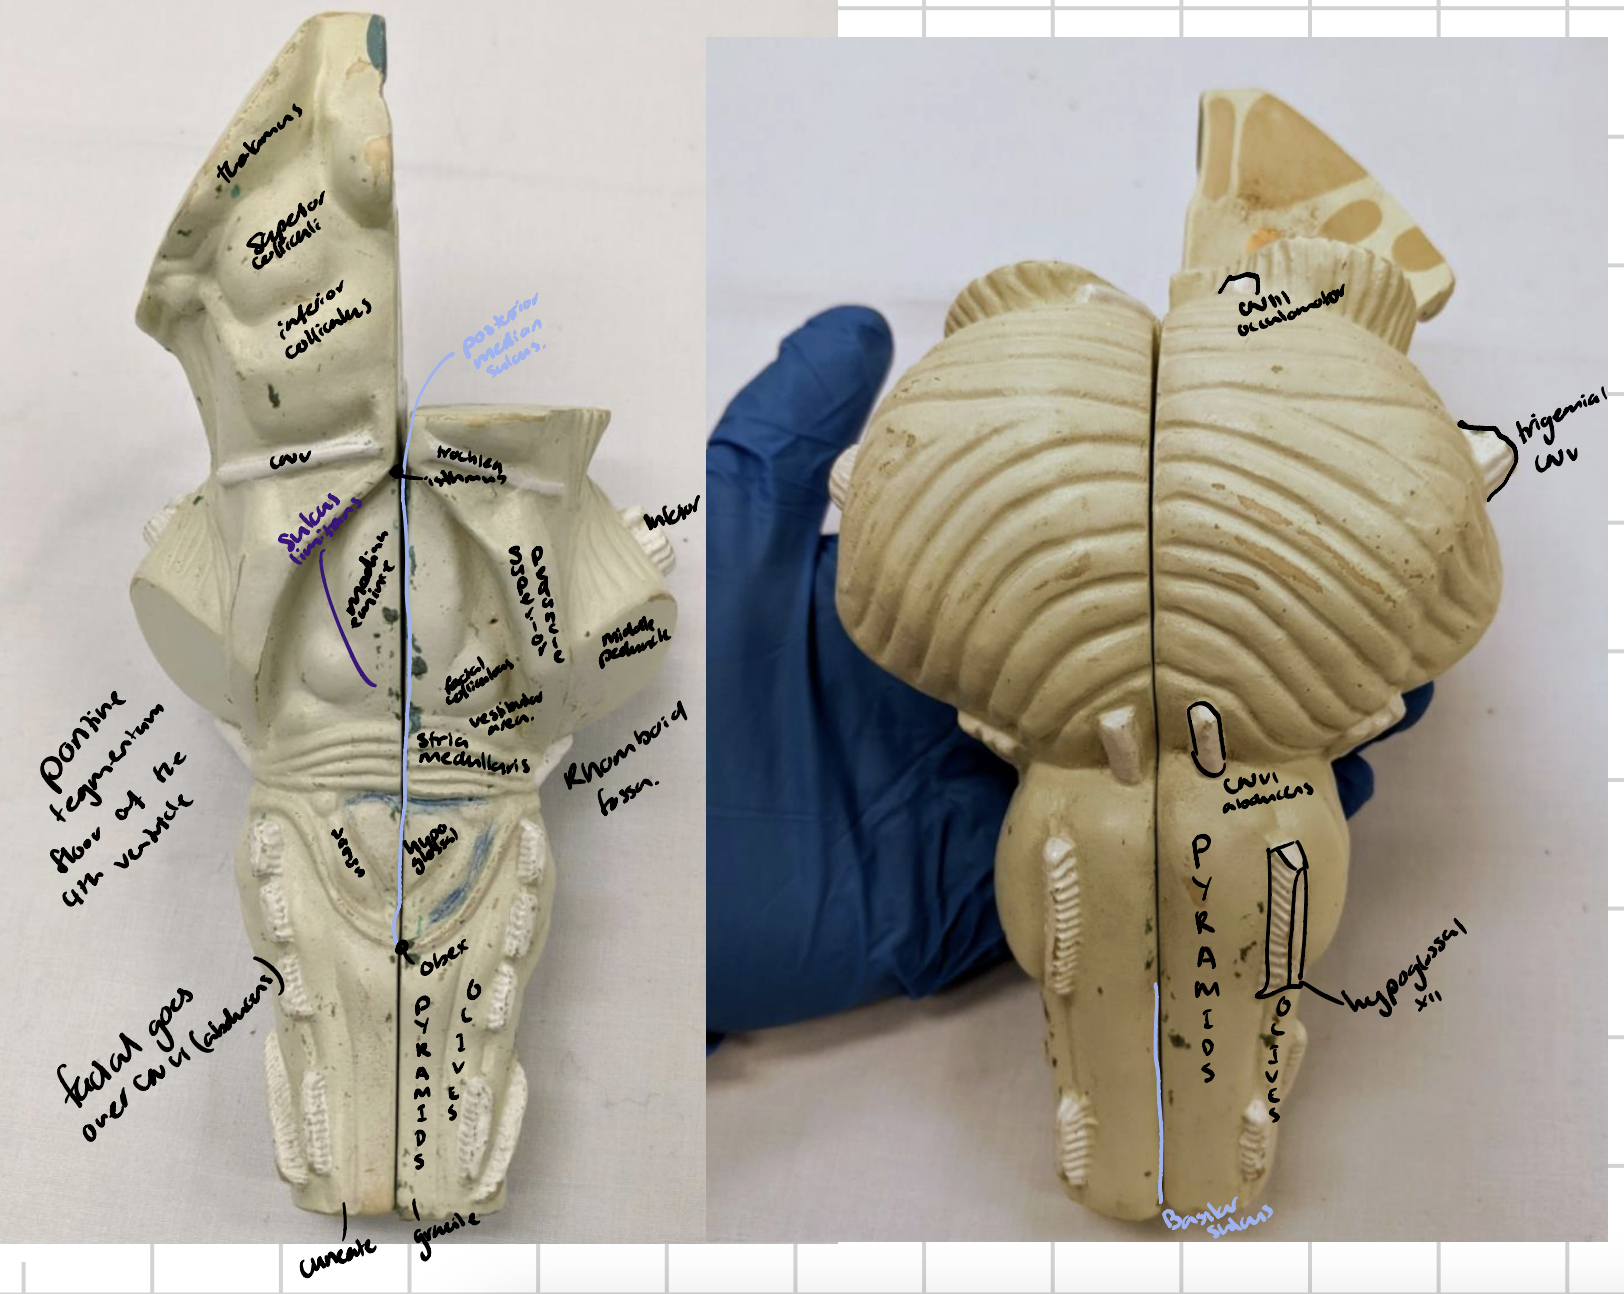

Anterior median fissure

Posterior median sulcus

Orientations of brain

Cerebellum

Anterior lobe of cerebellum

Horizontal fissure

Posterior lobe of cerebellum

Cerebellar tonsils

Posterolateral fissure

Superior medullary velum

Arbor vitae

Folia